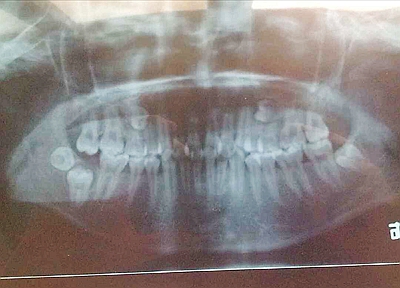

埋伏牙

牙齒萌出期已過(guò)而仍在頜骨組織中未能萌出的牙齒稱(chēng)為埋伏牙(embeded teeth)。

臨床多見(jiàn)于第三磨牙,其次為上頜尖牙,第二雙尖牙和額外牙等,有時(shí)有雙側(cè)的埋伏牙。一般由X光片檢查發(fā)現(xiàn)。在上頜中切牙之間,常有額外牙埋伏,可使兩個(gè)中切牙之間間隙加寬。埋伏牙可對(duì)相鄰的牙齒產(chǎn)生壓迫癥狀,如第二磨牙受埋伏的第三磨牙壓迫,發(fā)生牙根吸收,引起疼痛并繼發(fā)牙髓炎和根尖周炎。偶見(jiàn)多年戴總義齒的老年患者,有埋伏牙的萌出。